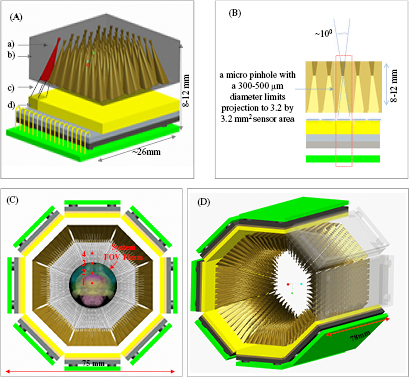

We have recently proposed an inverted-compound eye (ICE) gamma camera design (Lai et al 2013) for use with the MRC-SPECT-II system (figure 1). Each ICE camera uses a CZT or CdTe detector with a sensor area of 2.56 × 2.56 cm2 coupled to an aperture with 8 × 8 pinholes, each with a diameter of 300–500 μm (300 μm in this study). The shape of each pinhole restricts the projection from the object to a small area of around 3.2 mm × 3.2 mm on the detector. Each pinhole and its corresponding effective detector area form a micro-pinhole-camera-element (MCE). In our current design, each single ICE camera module has 64 MCEs.

Figure 1. Initial design of the ICE module for SPECT imaging. In sub-figure (A), (a) the micro pinhole; (b) ICE aperture with 8 × 8 pinholes; (c) cone of pinhole restricting the projection to 3.2 mm × 3.2 mm sensing area; (d) CZT/CdTe detector with area 2.56 × 2.56 cm2. (B) Cross section of the ICE unit. (C) Transverse view of the MRC-SPECT-II system. The four selected points are used to study angular sampling and geometrical sensitivity. Point 1, Point 2, Point 3 and Point 4 are 0 mm, 2.5 mm, 5 mm and 7.5 mm away from the center of the FOV; the brain model is used with permission of the Allen Institute for Brain Science (Lein et al 2007, Allen Mouse Brain Atlas 2018). (D) 3D drawing of the MRC-SPECT-II system.

Standard image High-resolution imageThe current design of the MRC-SPECT-II system is also shown in figure 1. It has three detector rings along the axial direction, and each ring has eight ICE-camera modules. This gives a total of 24 modules and 1536 MCEs. Since each MCE has a small open angle and covers a fraction of the FOV, the distribution of the MCEs and their orientation could be critical in achieving a reasonable FOV and adequate angular sampling.

Within the eight ICE camera modules in a ring, there are in effect eight rings of MCEs along the axial direction. These rings focus on a FOV with a 1 cm diameter in the axial direction and provide a relatively uniform angular coverage. In the transverse direction, the MCEs in the first ring have all been designed so that the left boundaries of their individual angular coverage are always tangential to the left boundary of the system FOV. For each MCE in the second ring, the right boundary of its FOV is tangential to the right boundary of the system FOV. The 1st, 3rd, 5th and 7th rings of the MCEs are designed in a similar way to bias towards the left-hand side of the system-FOV, and the 2nd, 4th, 6th and 8th rings of the MCEs to bias towards its right-hand side. As we will show later in section 3.1, this design offers a relatively uniform angular sampling in an ultra-compact detection system.